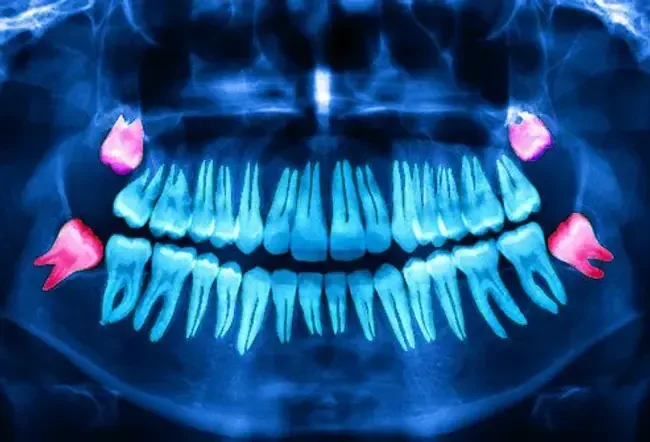

Dents de sagesse impactées

Qu'est-ce qu'une dent de sagesse impactée? Souvent, vos dents de sagesse ne sortent pas de la ligne de gencive (le terme médical est «éclaté») comme il le devrait. Parfois, les dents de sagesse poussent en pressant tordues contre ou loin des autres dents et sont appelés «impactés». Les estimations de la fréquence à laquelle les nouvelles dents de sagesse sont affectées varient considérablement. Certains avis indiquent que plus de 70% de toutes les nouvelles troisième molaires sont touchées tandis que d'autres disent moins de 40%. Ce problème conduit parfois à l'inflammation et à l'infection de la douleur mais pas toujours.

Une étude a montré qu'environ 12% des dents de sagesse touchées comprenaient des symptômes plus graves. Il est traditionnellement soutenu que les dents de sagesse impactées se pressent d'autres dents les jetant hors de l'alignement. Cependant, il a été soutenu que, parce que les dents de sagesse se développent à partir du tissu spongieux près de la mâchoire sans soutien fort, ils ne peuvent pas ancrer et perturber les autres dents qui sont plus fermement enracinées.